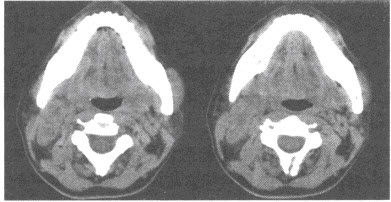

患者,男,17岁。因左下肢疼痛2个月入院,查体:左小腿中段局部肿胀,组织增厚较硬,有压痛,局部皮温稍高。体温38.2℃,实验室检查:WBC://13.8×10/L,N:78%;X线平片见下图。

(多选题)根据以上临床资料及影像学检查,需要考虑哪些疾病()

A:急性骨髓炎

B:转移性神经母细胞瘤

C:骨干结核

D:尤因肉瘤

E:骨髓瘤

F:骨肉瘤